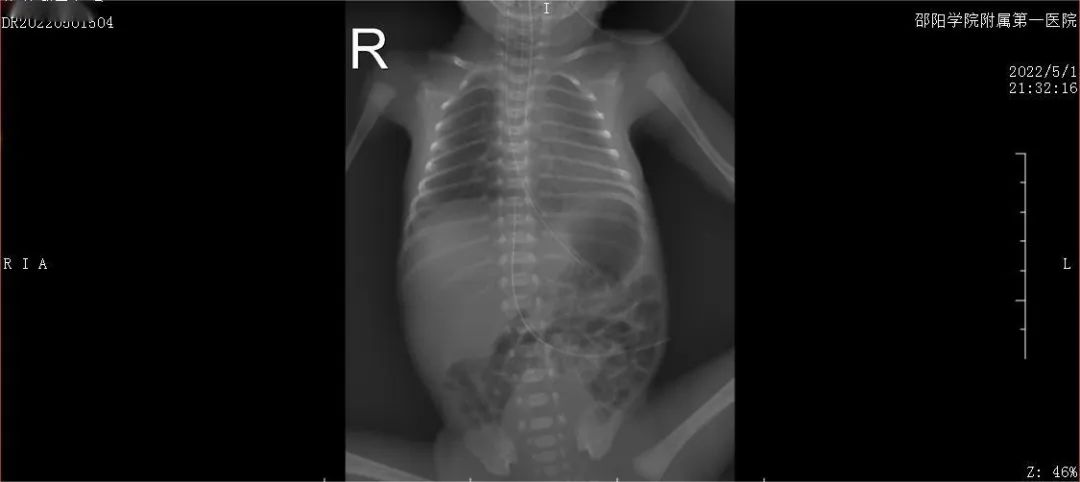

胸片检查:生后6小时(第一次PS后):双肺纹理稍增粗,双肺透亮度稍减低,双肺野可见散在斑片状模糊影。上腹部可见UVC管影,尖端位于T8/9椎间隙水平;生后24小时(第二次PS后):双肺纹理增多、增粗,模糊,右肺透亮度稍减低。与老片对比,透亮度较前增高。第21天:双肺纹理增多,双肺透亮度稍减低,双肺可见多发小斑片状模糊影,右上肺野可见片状致密影。心脏超声:第4天:心脏彩超:卵圆孔未闭、动脉导管未闭(PDA,3.5mm)。第8天:心脏彩超:卵圆孔未闭、动脉导管未闭(1.7mm)。第13天:心脏彩超:卵圆孔未闭,三尖瓣轻度返流。头颅B超:2次颅内超声未见明显异常声像。头颅磁共振平扫(MRI)(生后50天):符合早产儿脑改变。听性脑干及耳声发射双侧通过。小儿广域眼底摄像:双眼视网膜血管未完全化。

生后6小时(第一剂PS后)